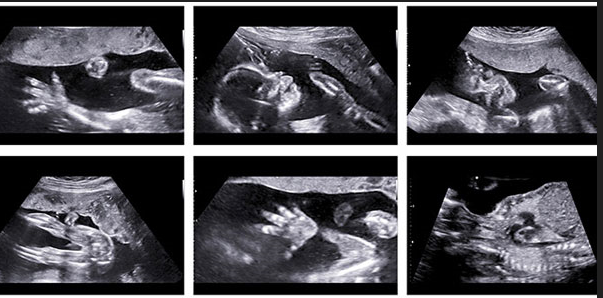

Early anomaly scan/Anomaly scan

Both Early Anomaly Scan and Anomaly Scan are ultrasound scans during pregnancy that help detect abnormalities in the developing fetus.